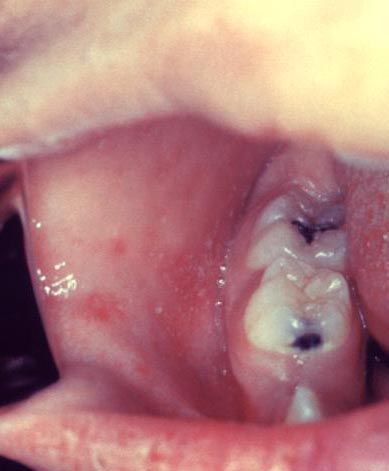

Measles is an acute viral respiratory illness. It is characterized by a prodrome of fever (as high as 105°F) and malaise, cough, coryza, and conjunctivitis -the three “C”s -, a pathognomonic enanthema (Koplik spots) followed by a maculopapular rash. The rash usually appears about 14 days after a person is exposed. The rash spreads from the head to the trunk to the lower extremities. Patients are considered to be contagious from 4 days before to 4 days after the rash appears. Of note, sometimes immunocompromised patients do not develop the rash.

Photos